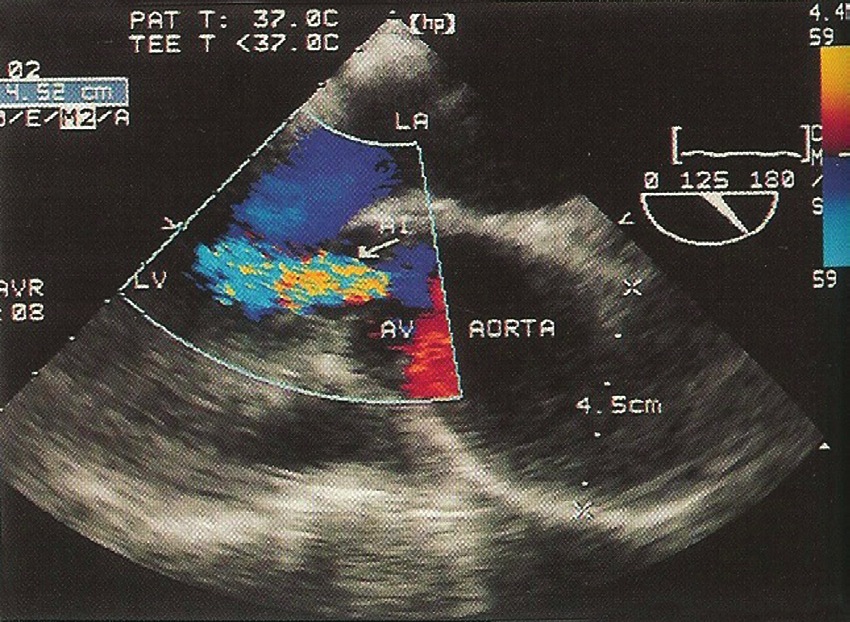

Respecto al primero de estos puntos, la ponderación de la insuficiencia requiere en primer lugar del análisis de la morfología valvular y luego, la integración de una serie de variables del doppler-color y espectrales, que cuantifican en forma precisa el grado de insuficiencia (Figuras 4 y 5). Entre ellos están:

Figura 4 Insuficiencia aortica bajo ecocardiografía transesofágica – Jet de insuficiencia aórtica en una ecocardiografía transesofágica en visión medio-esofágica en 120º.